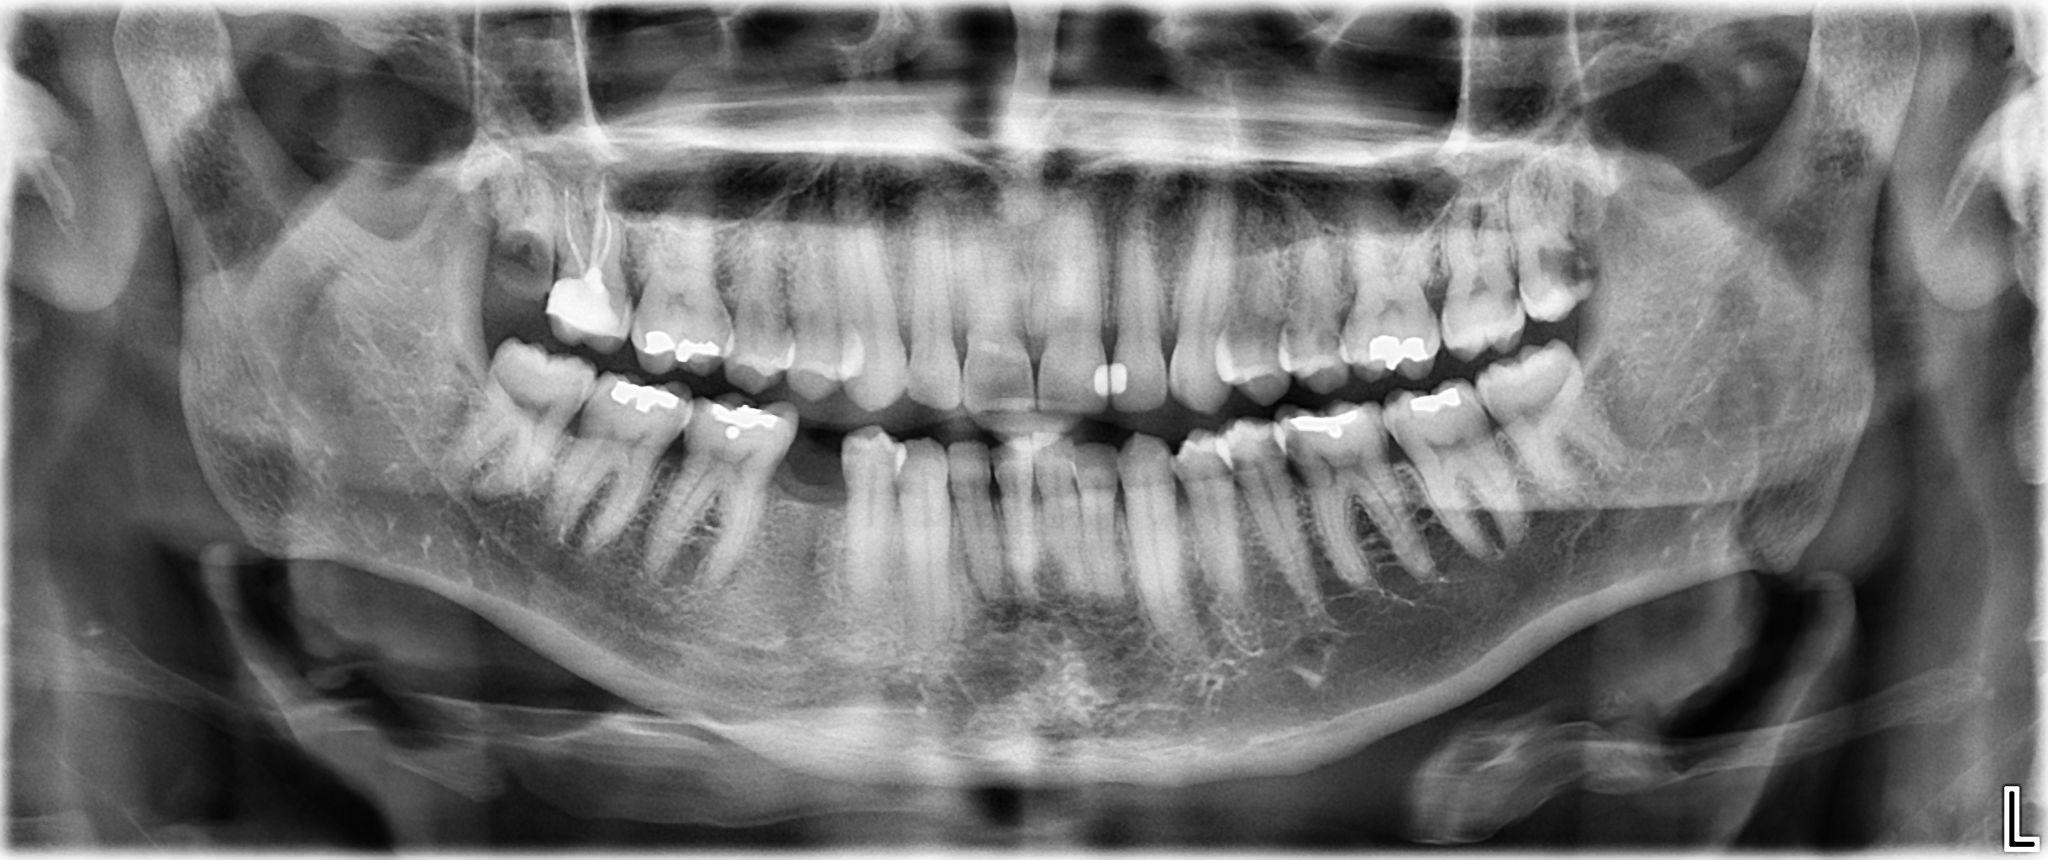

9. What options can be selected for the first quadrant of this panoramic X ray?

10. What options can be selected for the second quadrant of this panoramic X ray?

11. What options can be selected for the third quadrant of this panoramic X ray?

12. What options can be selected for the forth quadrant of this panoramic X ray?